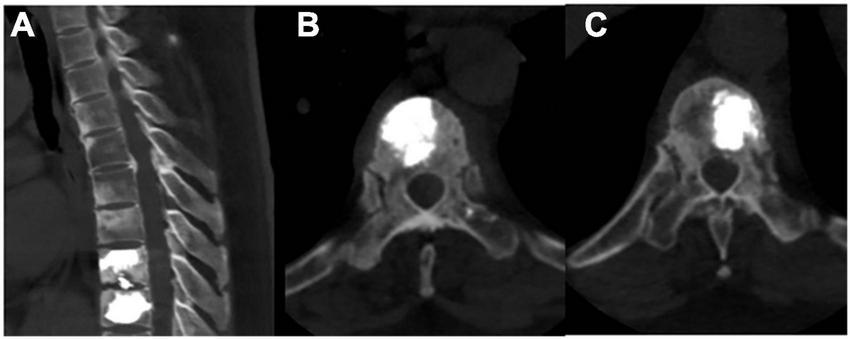

FIGURE 4

Post-operative radiographic images (A–C). (A–C) Post-operative thoracic CT revealed that the bone cement in T8 and T9 vertebrae was well dispersed.

A 52-year-old female patient who had a sex-month history of back pain. The patient took NSAIDs to relieve pain symptoms. However, the patient did not experience significant relief of pain symptoms after taking NSAIDs. More seriously, the patient’s symptoms worsened. The patient failed to walk due to progressive symptoms, and she had to stay in bed due to severe back pain. More treatments were not taken. The patient had difficulty participating in social activities and looking after herself. Therefore, her husband had to take care of her. Eventually, the patient could not tolerate the back pain, and she had to come to our hospital for further treatment. The patient indicated that she had no similar medical history or family history of genetic disorders. The patient also denied the presence of human leukocyte antigen B27 (HLA-B27) in her family history. Physical examination showed back tenderness pain. Palmoplantar pustulosis was observed on the hands and feet (Figures 1A, B). Achilles jerk reflex and knee jerk reflex were normal. The bowel and bladder functions were also normal. Plain radiographs revealed heterogeneous density of some thoracic vertebrae and osteophytes at the edges of some thoracic vertebrae (Figures 2A, B). Thoracic computed tomography (CT) scanning demonstrated cortical erosion, osteophyte, and osteosclerosis of some thoracic vertebrae (Figures 2C, D). The vertebral corner lesion and “kissing” appearance were observed on CT images. Thoracic magnetic resonance imaging (MRI) showed that low signal on T1-weighted images, high signal on T2-weighted images, and high signal on short time of inversion recovery (STIR) images of thoracic vertebrae with vertebral lesions (Figures 2E–I). Sacroiliac joint CT revealed unsmooth joint surface, extensive sclerosis of the bone and patchy low-density shadow (Figure 2J). Multifocal osteoarthritic lesions were found on whole-body bone scintigraphy (WBBS) (Figure 2K). Laboratory examination showed erythrocyte sedimentation rate (ESR) (120 mm/h) and C-reactive protein (10.58 mg/L) were significantly elevated, however, white blood cell count (8.83 × 109/L) and neutrophil percentage (68.8%) were normal. HLA-B27 was positive. No bacteria were found in the bacterial culture. Finally, the patient was diagnosed with SAPHO syndrome based on medical history, clinical symptoms, physical examination, laboratory examination, and radiographic findings. PVP was performed under local anesthesia to treat SAPHO syndrome with vertebral destruction. Puncture needles were placed into the T8 and T9 vertebral body. The puncture location was confirmed with the help of fluoroscopy. Subsequently, the working channel was established. Then, bone cement was slowly injected into the T8 and T9 vertebral body. And the working channel was removed. The pathological result demonstrated that lymphocyte infiltration (Figure 3). Antibiotics were injected intravenously within 24 h after the operation. NSAIDs were administered orally when she felt pain. Post-operative thoracic CT showed that the bone cement in T8 and T9 vertebrae was well dispersed (Figures 4A–C). The patient’s back pain was significantly relieved, post-operatively. On the second day after the surgery, the patient could easily leave the bed and move around. The patient’s symptoms gradually improved during the follow-up period. One year post-operatively, the patient returned to life freely and could participate in social activities. NSAIDs was sometimes taken to relieve pain. Interestingly, the palmoplantar pustulosis on the hands and feet disappeared (Figures 1C, D). Therefore, the patient was satisfied with the treatment.